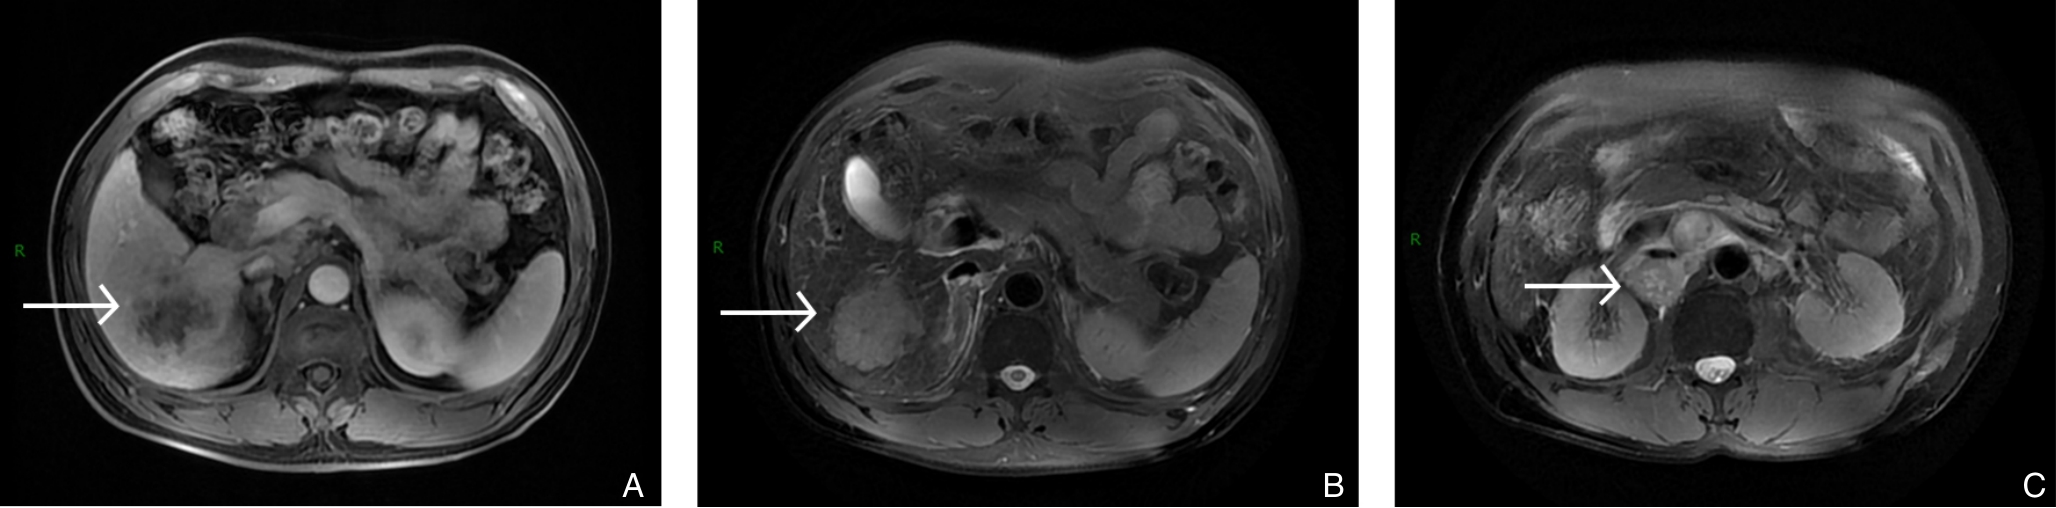

2025, 34(8):1783-1789. doi: 10.7659/j.issn.1005-6947.250076

摘要:背景与目的 肝内胆管癌(ICC)是一种起病隐匿、预后极差、初诊多为进展期的原发性肝癌,其治疗选择有限,预后差。本研究旨在探讨靶向治疗、免疫治疗与肝动脉灌注化疗(HAIC)联合应用于晚期ICC的转化治疗的潜力,为临床转化治疗提供参考。方法 回顾广东医科大学附属医院2021年11月收治的1例晚期ICC行靶向治疗、免疫治疗与HAIC联合治疗后成功转化并接受手术患者的诊治过程,并复习国内外相关文献。结果 患者为52岁男性,确诊为T2N1M0-Ⅲb期ICC。患者拒绝接受以吉西他滨联合顺铂为主的一线化疗方案,同意行靶向治疗联合免疫治疗与HAIC的综合治疗,在接受4个治疗周期后评估肿瘤达到部分缓解,具备实施根治性手术治疗的条件。患者随后接受了腹腔镜下肝S6段和部分S7段切除、胆囊切除以及肝门部和腹膜后淋巴结清扫术。术后患者规律行靶向免疫联合化疗的综合治疗方案。在疾病出现复发和转移后,化疗药物进行了相应调整。截至目前,患者无病生存期达15个月,总生存期超过3年。结论 靶向治疗、免疫治疗与HAIC三联方案可提高晚期ICC患者的转化机会并延长生存期,具有较好的安全性和临床应用前景,但其疗效仍需多中心研究进一步验证。